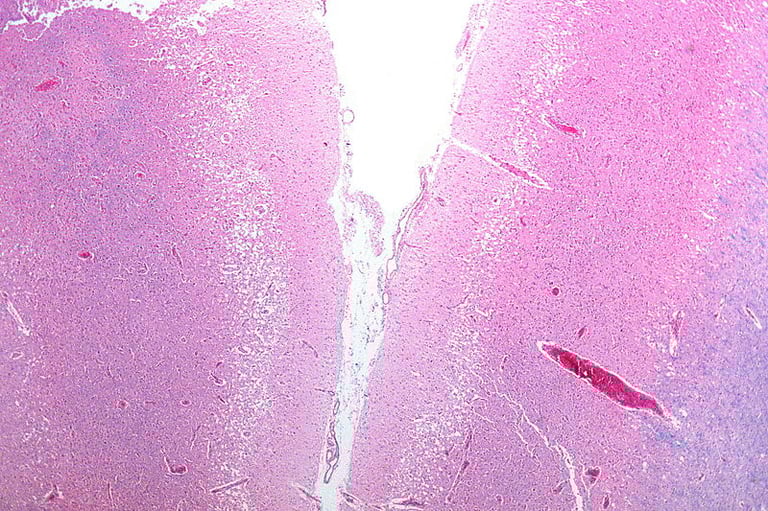

• The study utilized CT perfusion imaging to confirm salvageable brain tissue, allowing treatment beyond the previously established time limits of 4.5 hours in China and 3 to 4.5 hours in the U.S.